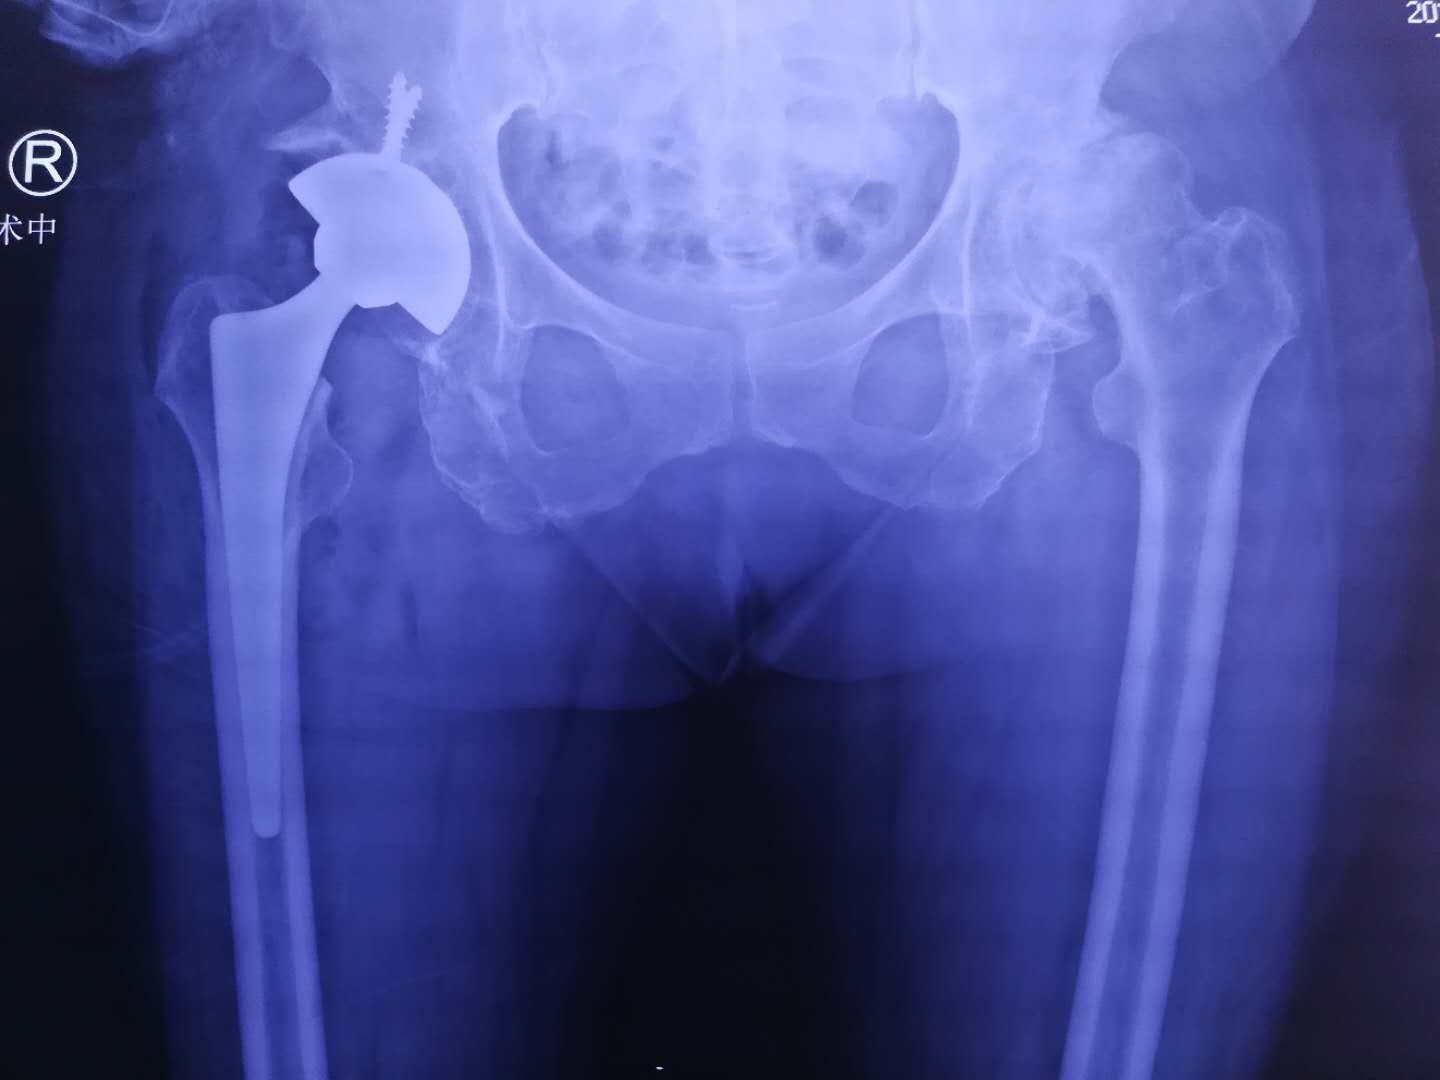

术前

郝医生一听他这么能喝酒,点点头,安排他摄片,果然,显示右侧股骨头坏死,需要做全髋

关节置换。

术后

昨天,郝亮技术团队给李师傅施行了全髋关节置换手术,手术很顺利,如今,李师傅正在关节病区康复。